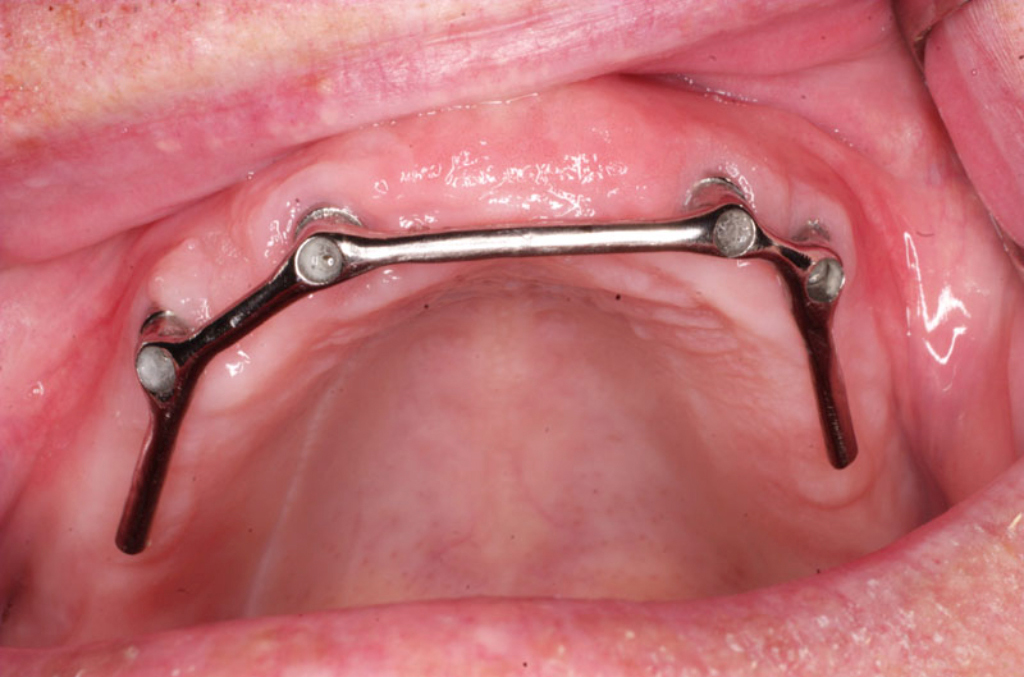

Třmeny

Kulové attachmenty

Sub-Tec Locator®

Bezzubá čelist je hlavní indikací pro ošetření pomocí implantátů. Zejména celkové zubní náhrady v dolní čelisti mají velice nízkou stabilitu a držení díky velkému úbytku kosti.

S pomocí zubních implantátů můžeme díky různým kotevním systémům (třmeny, kulové hlavy, Locatory) zajistit stabilitu a držení protézy nebo při použití většího počtu implantátů zhotovit pevné náhrady – můstky nalepené nebo našroubované na pevno na implantáty.

S těmito typy náhrad můžeme dosáhnout perfektní funkci, výbornou estetiku, fonetiku a současně zajistit u pacienta možnost dobré hygienickou péče a čištění, která je pro životnost implantátů velice důležitá.